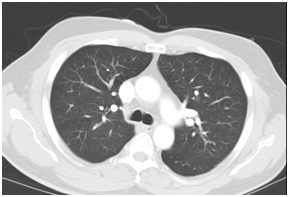

In view of the elevated Troponin I, the patient was initially treated as for Non-ST elevated myocardial infarction (NSTEMI). He was immediately started upon dual anti-platelet therapy together with low molecular weight heparin and subsequently underwent an emergent coronary angiogram which showed minor coronary artery disease. Computed Tomography of Pulmonary Arteries was also performed which showed no evidence of pulmonary embolism (Figure 2). The anti-platelet and low molecular weight heparin was then stopped. However, his gastro-intestinal symptoms worsened and he started to spike a temperature once more in the ward. He complained of persistent abdominal pain despite bowel clearance with laxatives. Computed Tomography of Abdomen and Pelvis was performed. The result showed long segment rectal wall thickening seen with peri-rectal fat stranding which was initially thought to be related to aggressive laxative consumption , but malignancy and infection should be ruled out with suggestion of endoscopy; extensive omental fat stranding, most prominent in the upper abdomen abutting the anterior wall of the transverse colon where there was thickening of the anterior transverse colonic wall to rule out possibility of underlying malignancy; peritoneal fat stranding and nodularity seen with minimal ascites; small volume but rounded inferior mensenteric and para-aortic lymph nodes seen.

Figure 5CT Pulmonary Angiogram: A few non- specific pulmonary nodules are seen e.g. in the anterior segment of the right upper lobe.

Figure 5CTPA: Thrombus in the segmental right lower lobar pulmonary artery, and anterior segmental branch of the left lower lobe pulmonary artery. There is right ventricular strain and infarct in the right lung base.